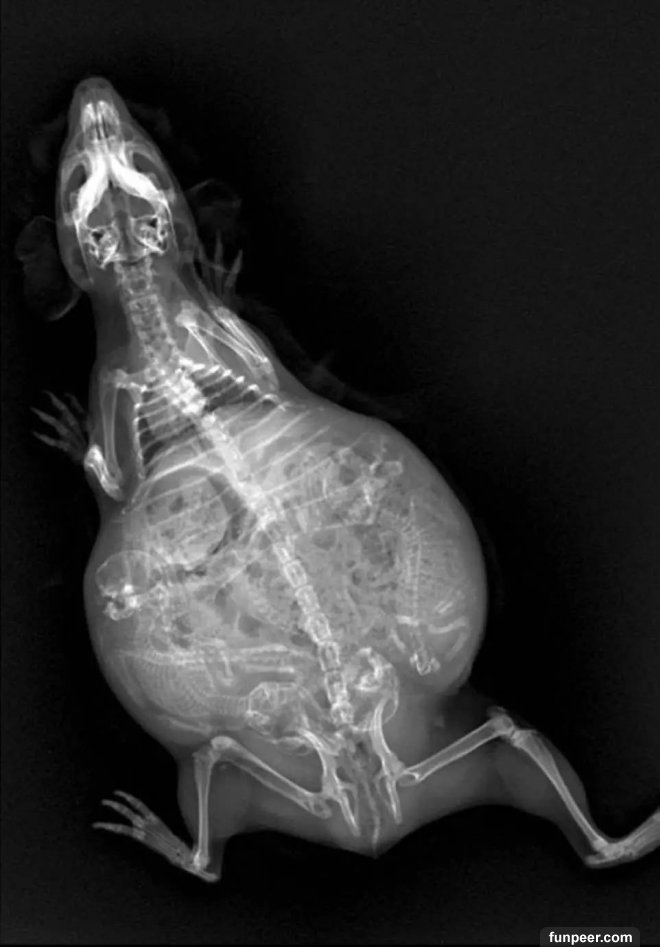

豚鼠的整個身體似乎都擠滿了孩子

![]()